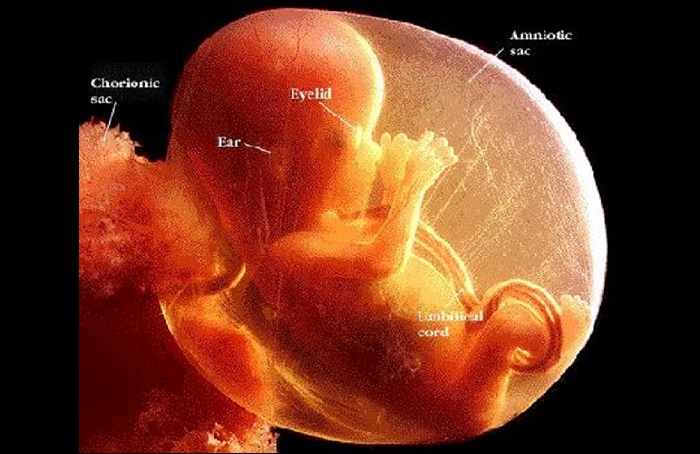

E perché le dicevano che i bambini in grembo non sono bambini...

“Nel 1983 ho tenuto tra le mani un bambino abortito spontaneamente di 14 settimane. Non era un ammasso di tessuto, o un coagulo di sangue, o un grumo di cellule. Era un bambino piccolo, che ha scalciato e agitato le braccia debolmente cercando di respirare. Quel piccolo bambino voleva vivere. Mi ha spezzato il cuore.

Sono diventata pro-life da allora, perché in quel momento ho visto la verità. “